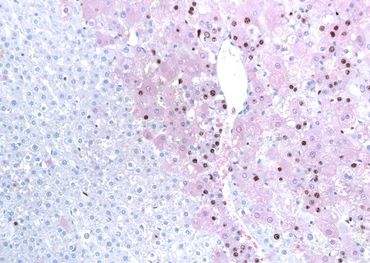

Enumerating ovarian follicles is an effective way to estimate the extent of ovarian toxicity in female rodents exposed to xenobiotics. Differential follicle counts are useful in safety assessment bioassays and in interspecies extrapolation of ovarian toxicity. Counting the follicles in H&E-stained sections is labor intensive, tedious, and costly. Here, at TPA, we demonstrated that in rat formalin-fixed, paraffin-embedded ovary sections follicles of all degrees of maturity can be visualized by the use of antibody directed against proliferating cell nuclear antigen (PCNA). Follicles are easily distinguished from ovarian background with the ability to detect and identify primordial follicles being enhanced. This translates into a significant decrease in variability of follicle counts, labor, and cost.

PCNA-stained oocytes of primordial follicles in rat ovary (PCNA IHC). x160